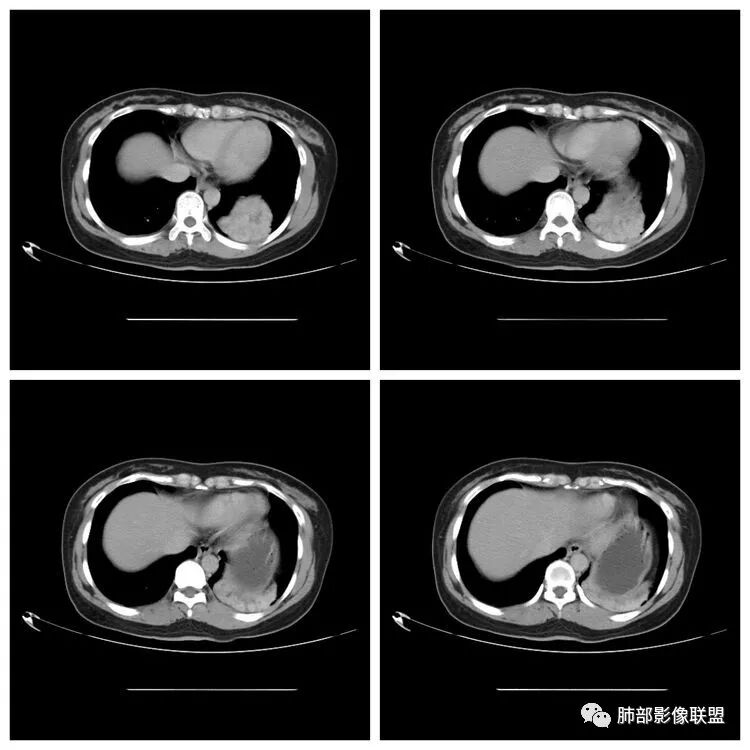

下面看第三部分了,3月20日补增强扫描:

M-Imaging :错了,这么大,膈肌后方南边:定位?定性?Shelia:肺外。感觉病灶是个扁平状,虽然没有蛇纹血管征,但是延迟强化,怀疑纤维来源,考虑sft

宇宙星空:延迟明显强化,其内可见条索状低密度,支持SFT

lmg:其内可见血管穿行吧,考虑SFT

一米阳光:与膈胸膜关系密切,肺受压。考虑SFT